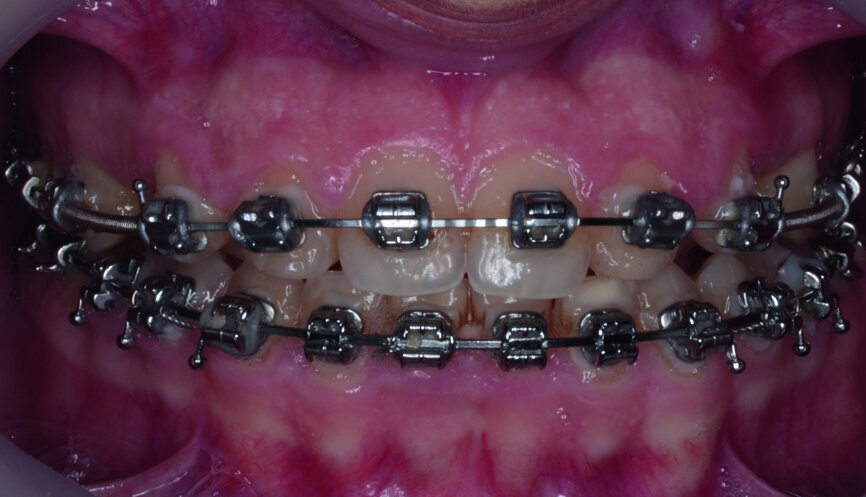

- Upper bracket placement (Fig. 22): level and align the gingival margins, and correct the torque on the upper canines who will substitute the lateral incisors.

- Implants space opening: substitute laterals with canines (Figs. 23–25) and substitute canines with first premolars (Figs. 26–28).

- Finishing and occlusal settling (Figs. 29–31).